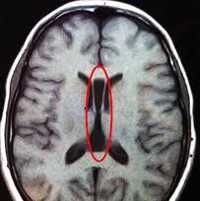

- Нейросонография. При ультразвуковом сканировании головного мозга определяется крупное кистозное образование в задней части черепной коробки. На УЗИ мозжечковый червь не визуализируется, недоразвитые полушария мозжечка раздвинуты, желудочковая система мозга расширена и деформирована.

- МРТ головного мозга. Магнитно-резонансная томография в сагиттальной и аксиллярной проекции демонстрирует расширение четвертого желудочка, грубые нарушения развития мозжечка, другие структурные аномалии.